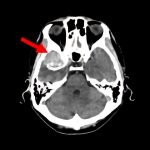

断層撮影